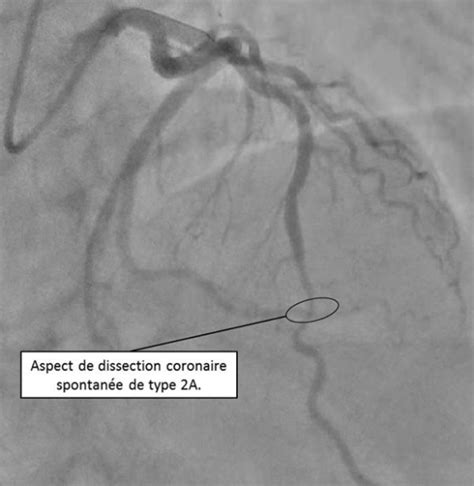

La Coronarographie : Une Imagerie Spécifique des Artères Coronaires

Bien que distincte de l'analyse de la silhouette médiastinale, la coronarographie est mentionnée dans les informations fournies et mérite d'être brièvement évoquée pour compléter le tableau des imageries thoraciques. La coronarographie est l'examen de référence pour diagnostiquer la maladie coronarienne. Elle permet de visualiser le nombre, la localisation et la sévérité des sténoses des artères coronaires. Une sténose est définie par une réduction du calibre de la lumière coronaire supérieure à 50%, et considérée comme serrée au-delà de 70%. L'estimation visuelle des sténoses en pratique quotidienne a tendance à surestimer leur importance. L'aspect angiographique de la sténose est un élément prédictif du risque lors d'une éventuelle angioplastie.